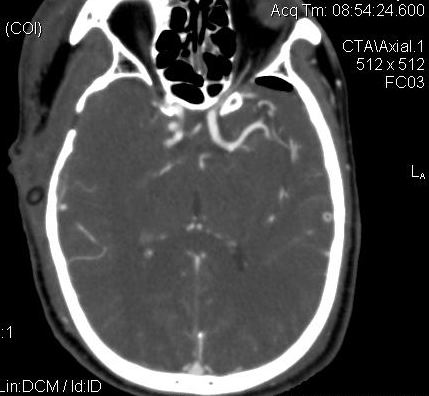

男.60岁,渐进性意识不清,ct检查双侧额颞顶部硬膜下血肿,开颅术后行脑血管cta,大脑中动脉起始部见一瘤状血管扩张。请各位老师留下宝贵意见

太常见了,报动脉瘤就可以

符合动脉瘤表现。

符合动脉瘤表现。

动脉瘤。

颅内动脉瘤。

后重建做得不是很好看,要将维蒂斯环充分显示,最好在增加一个mip。这样不好定位。

小动脉瘤

典型

符合动脉瘤的表现

动脉瘤

符合动脉瘤表现。

小动脉瘤

典型